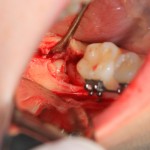

Итак, на фото вы видите шестерку и наклеенные брекеты. Последние несколько осложняют нашу работу, существует риск, что мы случайно один из брекетов оторвем — и об этом мы предупреждаем нашу пациентку.

Далее, разрез. Создаем доступ к зубу. Для этого используется повышающий наконечник с соответствующими фрезами. Вот они, восьмерка и семерка:

Чтобы аккуратно удалить восьмерку и не повредить соседний зуб, мы делим ее на две части. НИКАКИХ МОЛОТКОВ И ДОЛОТОВ))) Все делается, исключительно, с помощью фрез: